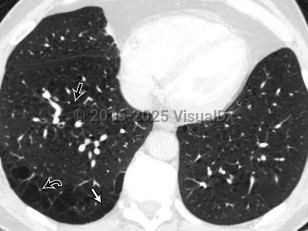

Pulmonary emphysema

Pulmonary emphysema is a type of chronic obstructive pulmonary disease (COPD) characterized by the loss of individual alveolar wall structures, resulting in larger and less efficient alveoli with air trapping. Shortness of breath begins gradually; it may take years for affected patients to seek treatment. Other findings include wheezing, cough, chest pain, cyanosis, and increased heart rate.